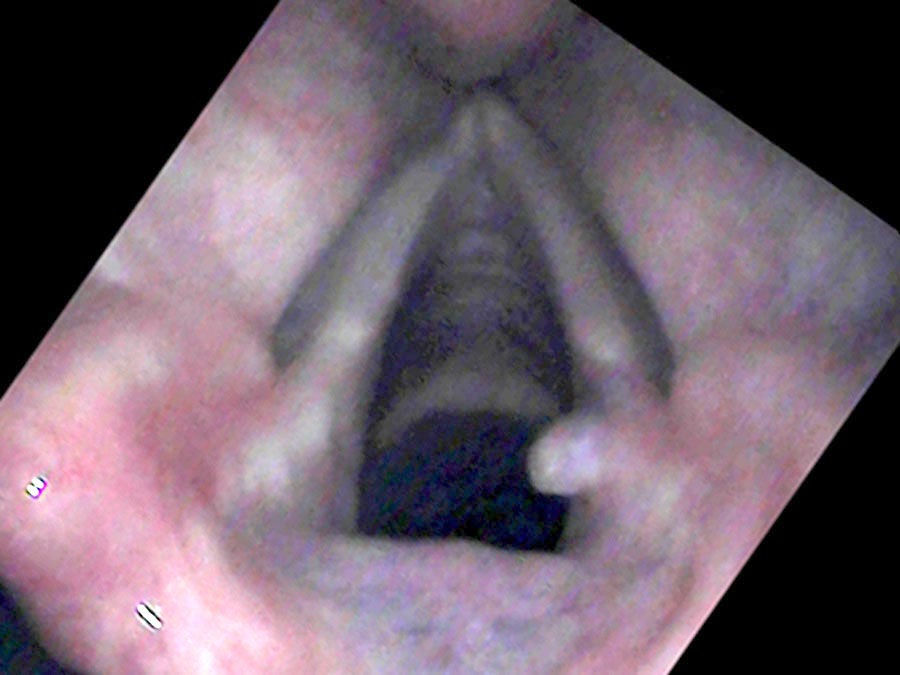

On endoscopy, there is a surprisingly large lump on the right vocal process — a yellow ball of tissue sitting just above an ulcerated groove in the cartilage.

It really isn’t a growth. It is a collection of blood vessels wound into a little ball — what surgeons call “proud flesh” when it forms on the outside of the body.

There is one particular type of vocal cord lesion that may start with a temporary pain and is located at the back of the larynx — most commonly on the cartilage called the vocal process of the arytenoid, right at the end of the vibrating portion of the vocal cord. It is not really a growth. Rather it is a collection of blood vessels wound into a little ball — called proud flesh when it forms on the outside of the body. When something traumatizes the mucosa, eroding through it and exposing the cartilage, an ulcer forms. Then granulation tissue heaps up around the traumatized point as a reaction to an open wound exposed to the bacteria of the mouth and throat.

From injury to resolution, granulomas follow a predictable evolution. New ulcers from overuse initially split into two parts where the opposite vocal process rests in a groove during closure. Gradually, granulation tissue heaps up around the traumatized point, forming a mass. In the middle of their lifespan granulomas become yellow or red and round. Later the mass tends to harden, become white and spherical, and the base narrows to a stalk. At this stage the granuloma may flip up out of the way during phonation and no longer impairs closure — so vocal capabilities testing can return to normal even while the granuloma is still present.